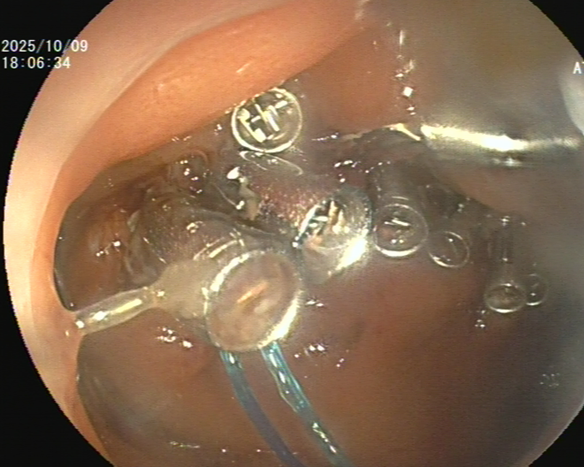

消化内科主任潘新智与患者及家属充分沟通后,为其实施了盲肠黏膜剥离术(ESD)。术中,团队克服了盲肠病变距离肛门远,肠壁薄、蠕动频繁、随呼吸波动大等困难,以微创方法为患者完整切除了盲肠巨大侧向发育型肿瘤,避免了外科手术。

术后病理报告证实病灶完整切除,基底及侧切缘均未见肿瘤细胞。